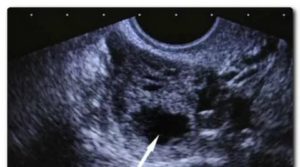

На УЗИ желтое тело определяется как округлое неоднородное образование.

Его видно и при методике исследования через брюшную стенку (трансабдоминальная методика УЗИ), но более достоверные результаты диагностики получают при трансвагинальном методе с использованием внутривагинального датчика.

Проведение УЗИ яичников позволяет изучить все параметры этой железы. Желтое тело на УЗИ имеет вид округлого неоднородного мешочка. С особым вниманием относятся к нему при следующих физиологических состояниях женского организма: